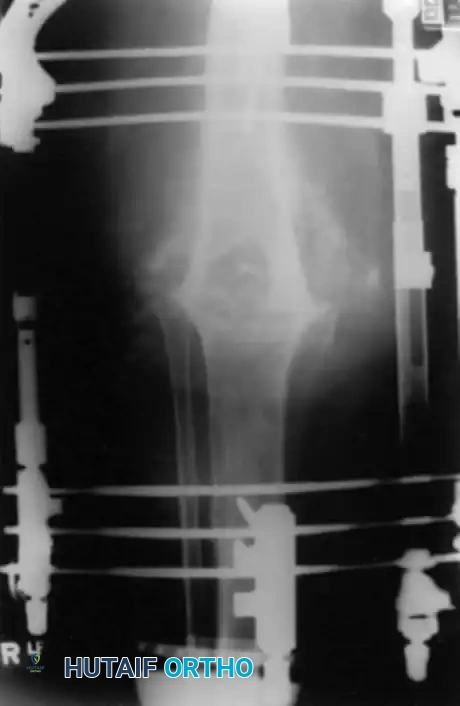

Radiographic appearance of a knee arthrodesis utilizing a long intramedullary nail following failed infected TKA.

Surgical Technique (IM Nailing):

1. Positioning: Supine on a radiolucent table.

2. Preparation: Remove all implants and cement. Prepare the femoral and tibial canals using flexible reamers.

3. Bone Apposition: Ensure flat, bleeding cancellous bone surfaces on both the distal femur and proximal tibia.

4. Implantation: Pass a long, custom or modular intramedullary nail antegrade through the femur into the tibia, applying compression across the arthrodesis site.